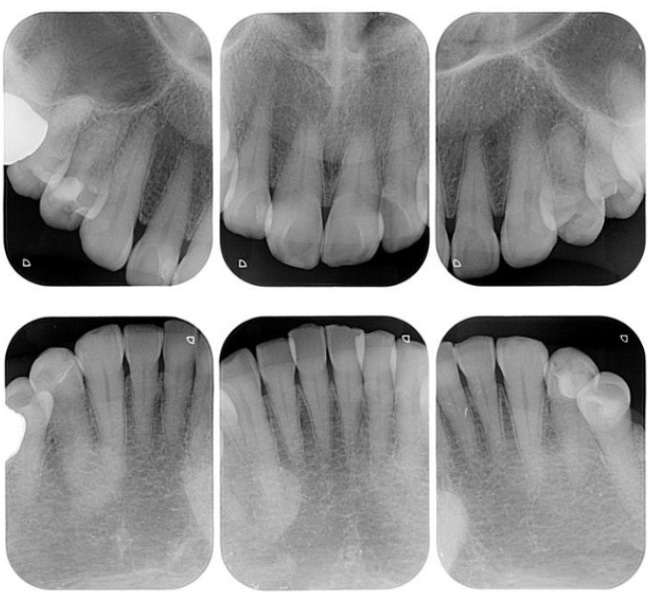

治療前

(レントゲン)

【レントゲン】左下奥歯のレントゲン所見

一番奥の歯(左下7番)は、被せ物の下の土台にヒビ(破折)が入っており、歯の内部と外部の両方から細菌感染が進んでいる「末期的な状態」です。周囲の骨が広範囲に溶け、大きな黒い影として写っています。

その手前の歯(左下6番)は、過去に根を分割する処置がされていますが、土台が根の方向からズレており、噛み合わせの強い力に耐えきれず地盤(骨)を半分以上失っています。

どちらの歯も、これ以上の補修では建物の重み(噛み合わせの力)を支えられず、放置すれば周囲の健康な骨までさらに溶かしてしまうため、将来を見据えて「戦略的な抜歯」を選択しました。